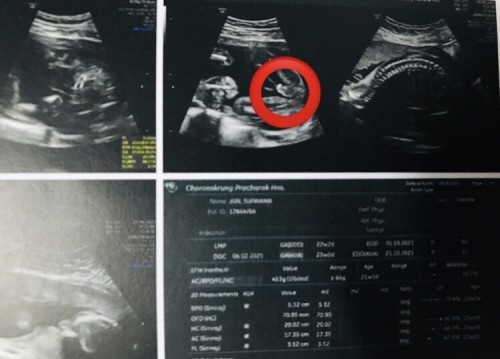

วันนี้หมอนัดไปอัลตราซาวด์ คิดไว้ว่าคงได้หญิงเพราะคนแรกผู้หญิง สรุปหมอซาวด์ได้ชายมาตื่นเต้นมากๆ จู๋กับไข่โผล่มาเลยค่ะ #ท้อง2 #22w3d #บ้านไหนได้ลูกชายบ้างค่ะ🥰

บ้านนี้ค่ะ คุณพ่อไปอย่างมั่นใจเลยว่าลูกสาวแน่ๆทำเองขนาดนี้ 🤣 แต่พอหมอซาวด์เห็นจู๋หมอทัก โอ้โหคุณแม่ นี่ไงจู๋ชัดๆเลย อีพ่อคือหน้าจ๋อยไปเลยค่ะ เพราะพนันกับแม่ไว้ แม่ลงข้างลูกชาย นางลงลูกสาวค่ะ เห็นบอกถ้าได้ลูกชายกลัวดื้อเหมือนตัวเอง 5555